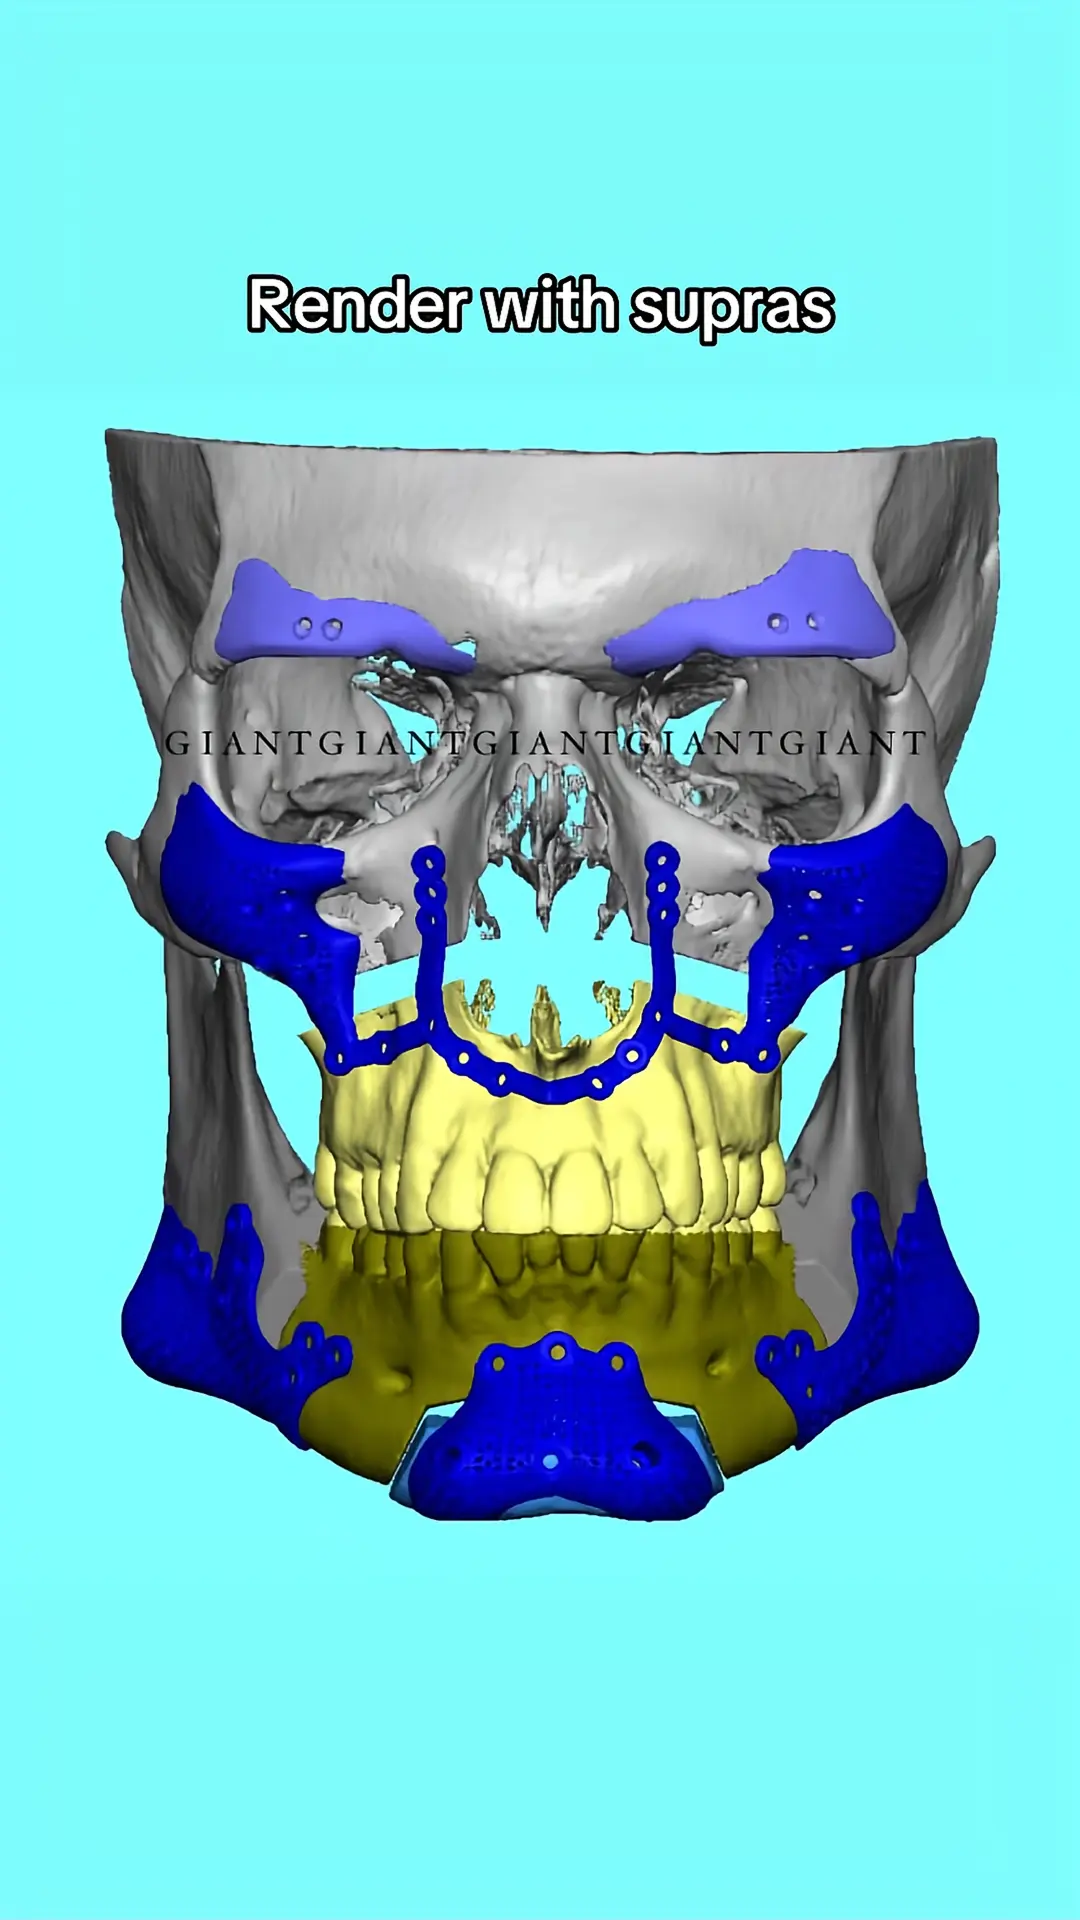

You can see there is already zygo implants they are like combined with metal plates that supposed to keep in place bonesHe should get zygo implants.

This is ideal and not dangerous